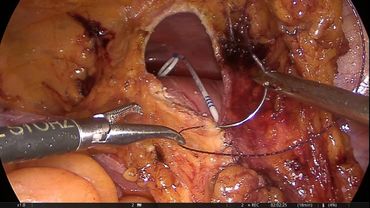

Retroperitoneal laparoscopic pyeloplasty (Right)

Ahmed M. Harraz, MSc, MD, MRCS, FRCS, EBUPublished at:

194Description: